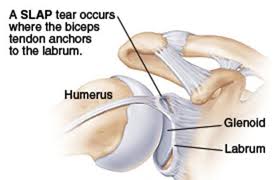

קרע בשוליים הסחוסיים של הפרק (labrum): פגיעה זו די שכיחה ובדרך-כלל נובעת מחבלה. המדובר בנזק לסחוס הנמצא בשולי המפגש בין הזרוע לשכמה.